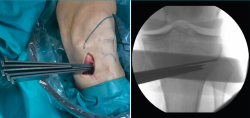

Figura 3. Se marcan los cortes de la osteotomía biplanar con un ángulo de 120°.

Posteriormente, bajo control radioscópico, se realiza la osteotomía apoyando la sierra por debajo de la aguja guía, llegando hasta 1 cm de la cortical lateral. Se introducen los escoplos para abrir la osteotomía (Figura 4). El primer escoplo, el más ancho, se introduce primero para comprobar el corte completo de la cortical posterior. Seguidamente, se coloca el medidor del ángulo de apertura (Figura 5A) y, a continuación, se introduce el distractor en la parte posterior de la osteotomía, evitando así un aumento de la PTP (Figura 5B). En este momento, se puede introducir en la apertura de la osteotomía el aloinjerto o sustituto óseo. Los autores utilizan aloinjerto óseo cuando la apertura es mayor de 10°. Antes de colocar y fijar la placa de osteotomía, se realiza el túnel tibial utilizando las herramientas artroscópicas clásicas (Figuras 6A y 6B). Al realizar una osteotomía biplanar, el corte es suficientemente distal como para permitir brocar el túnel tibial de la RLCA sin dificultades.

Figura 4. Colocación de escoplos de forma progresiva para realizar la apertura (una vez realizados los cortes con la sierra).

Figura 5. A: medición del ángulo de apertura de la osteotomía con el medidor; B: colocación del distractor en la parte posterior de la osteotomía, evitando así el aumento de la pendiente tibial posterior.